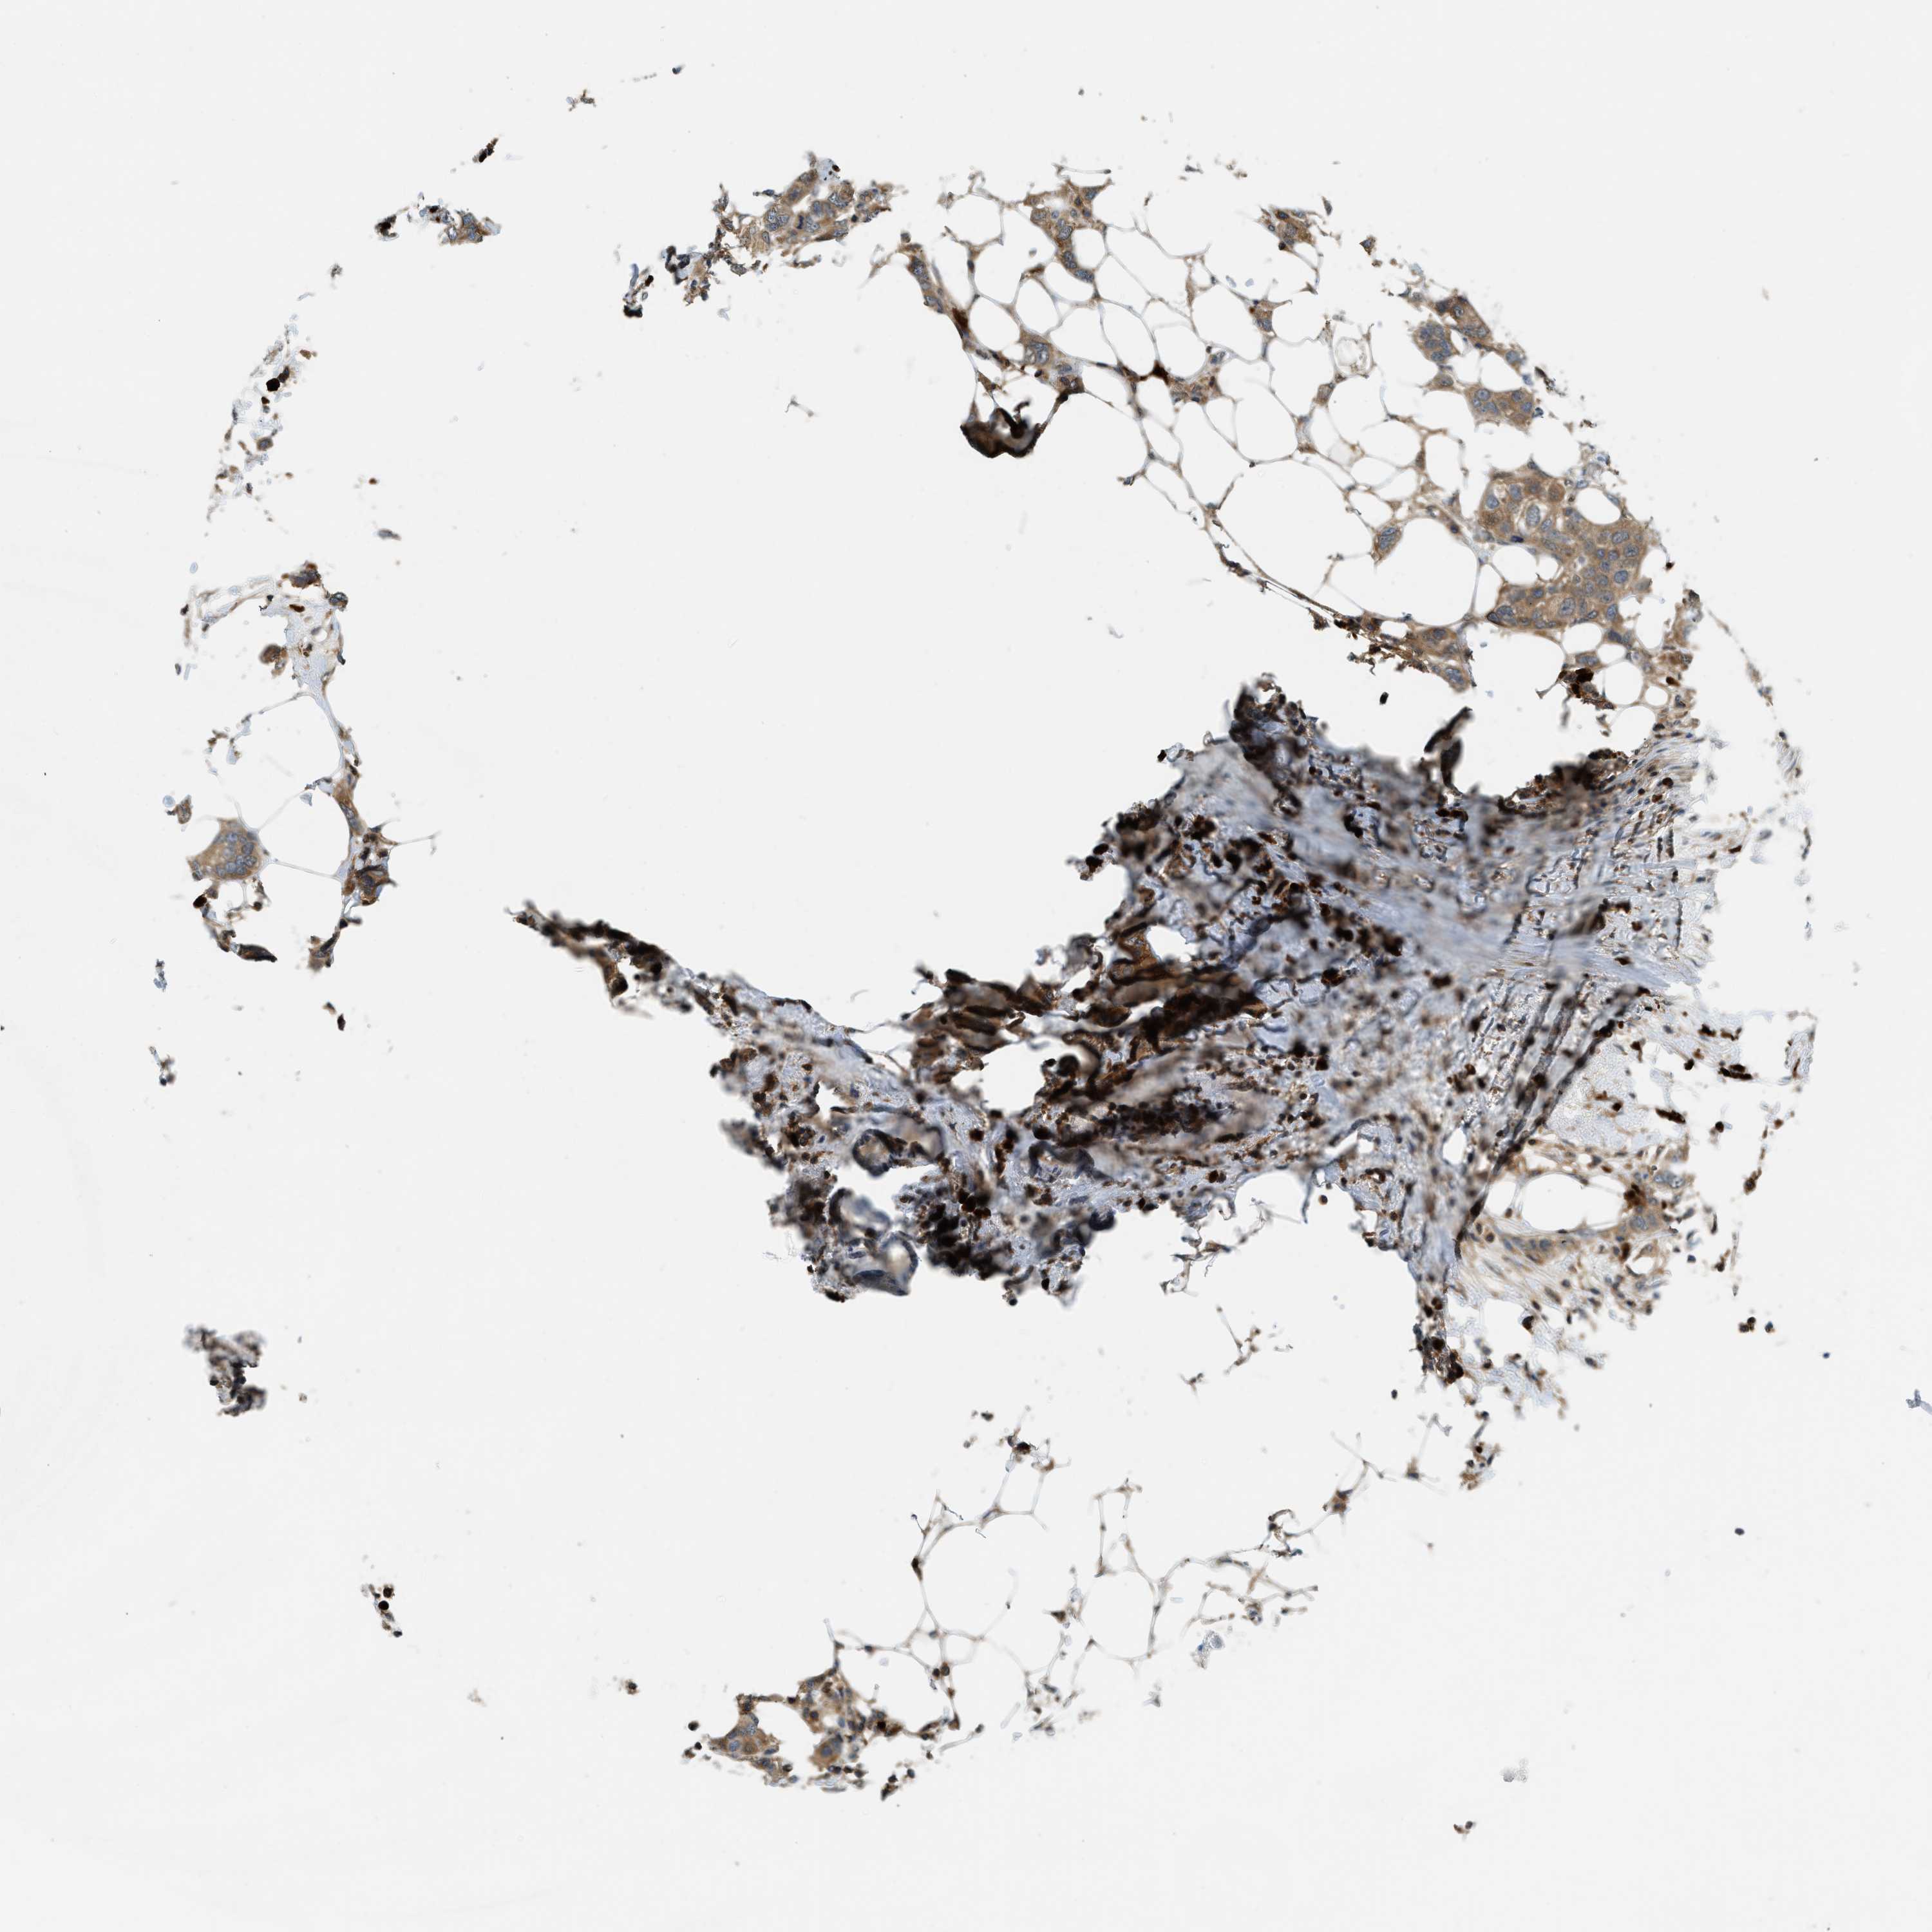

CANCER BREAST CANCER Show tissue menu

BRCA TCGA BRCA VALIDATION PROTEIN EXPRESSION